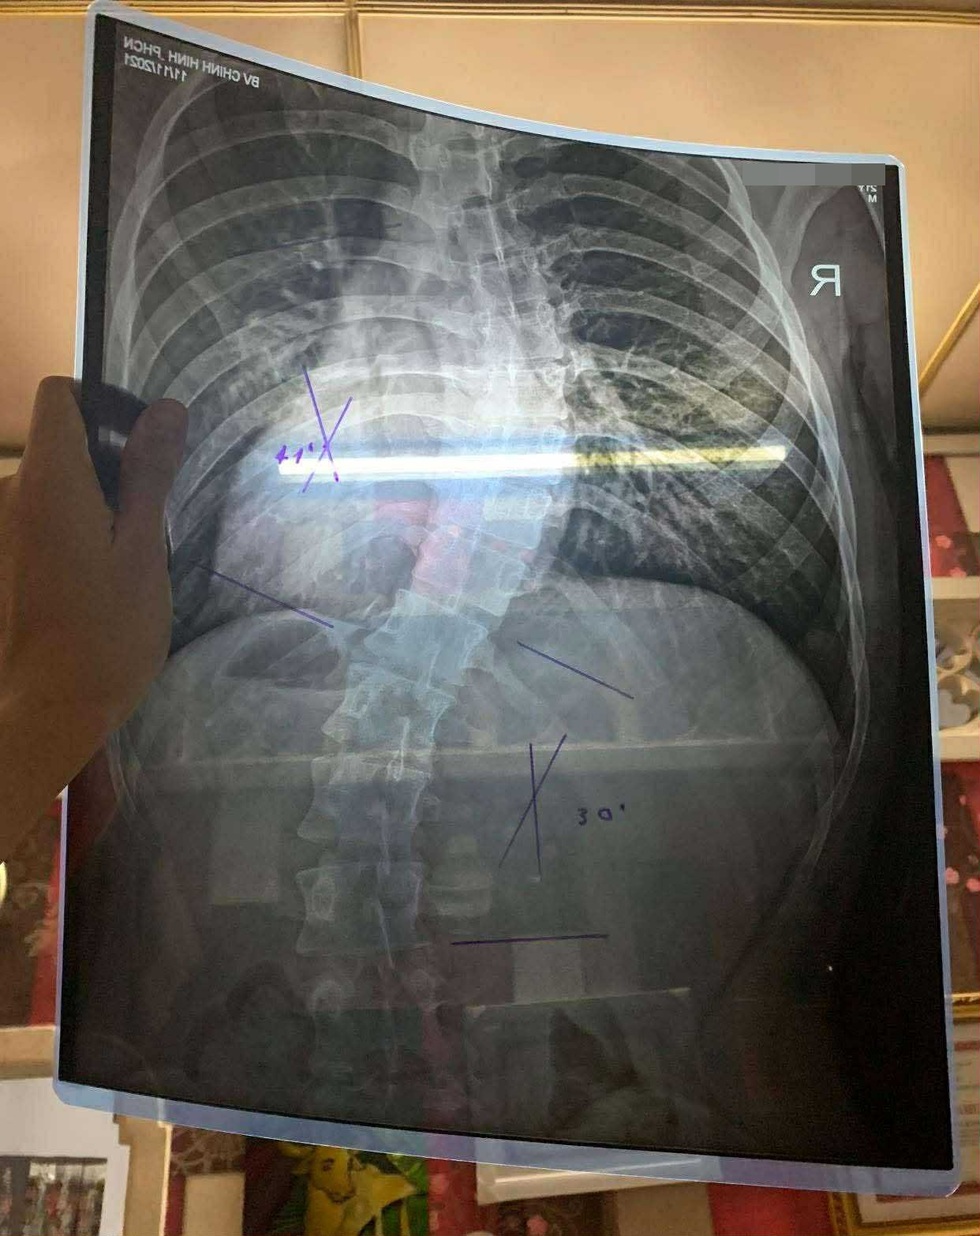

“Xương cột sống cong tới 40 độ thành hình chữ S rõ rệt. Sao giờ em mới đi khám? Xương cong thêm chút nữa là nguy cơ gãy cao lắm”, nghe bác sĩ nói, Mạnh tá hỏa, vì chưa từng nghĩ vấn đề tư thế lại nghiêm trọng đến vậy.

Hai điểm vẹo cột sống nặng được bác sĩ đánh dấu trên phim X-quang của Mạnh (Ảnh: NV).